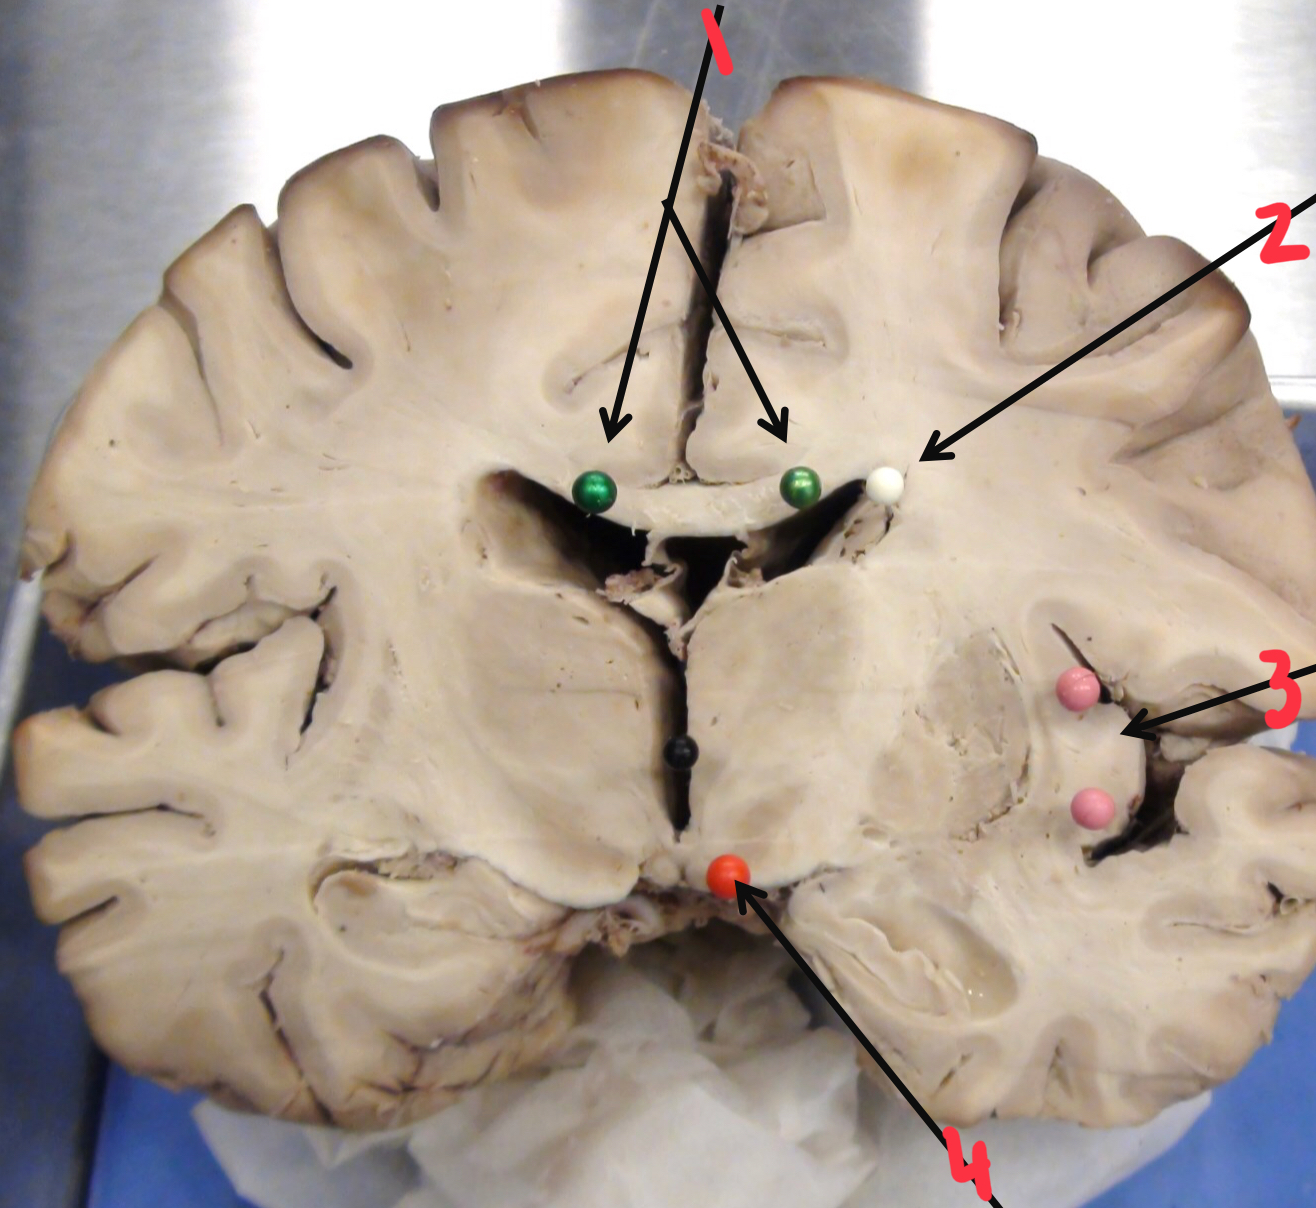

1

putamen

2

hippocampus

3

thalamus

4

internal capsule